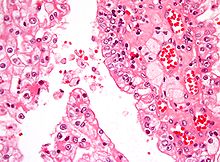

Micrograph showing the most common type of kidney cancer (clear cell renal cell carcinoma). H&E stain.